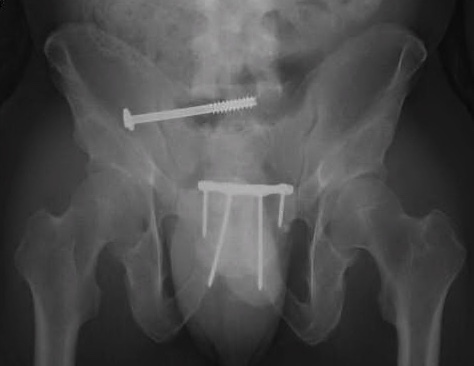

Chart review was undertaken to obtain basic demographic variables such as age, sex, smoking and diabetic history. Injury radiographs were reviewed to determine fracture type and Young-Burgess fracture classification. Preoperative and postoperative radiographs are demonstrated in figures 1A, 1B, 2A and 2B. Operative records were reviewed to determine which patients underwent screw removal and if any adverse intra-operative events occurred. Hospital charts and clinic charts were reviewed to document any postoperative complications and record pre and postoperative visual analog pain scales.